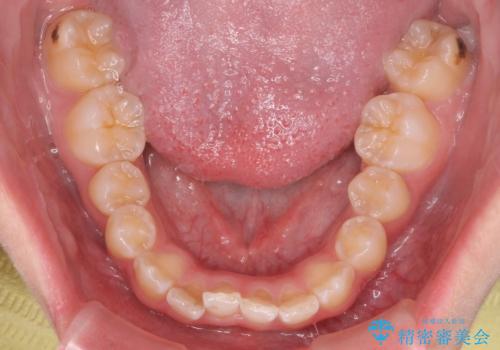

前歯の並び インビザライン 非抜歯で 深いかみ合わせの治療

- 前歯の並びを気にして来院。

上の前歯が内側に倒れこんでいました。

インビザラインで前歯の並びを整えています。

前歯の重なりが大きいいわゆる過蓋咬合を呈していましたが、ある程度適正な重なりにすることができました。